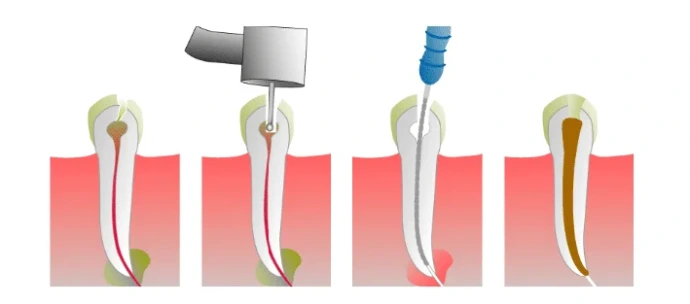

Root Canal Treatment